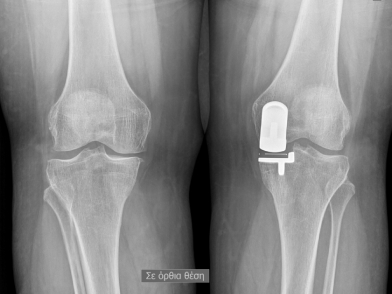

Η έσω μονοδιαμερισματική αρθροπλαστική γόνατος είναι αυτή που εκτελείται πιο συχνά, καθώς το μεγαλύτερο μέρος των δυνάμεων που ασκούνται στο γόνατο περνούν από το έσω διαμέρισμα άρα υπάρχει μεγαλύτερη φθορά. Η έξω μονοδιαμερισματική αρθροπλαστική γόνατος δεν εκτελείται τόσο συχνά καθώς το έξω είναι το λιγότερο συχνά προσβεβλημένο διαμέρισμα. Η αποκατάσταση είναι ταχύτερη και λιγότερο επώδυνη από μία ολική αρθροπλαστική ωστόσο η αναθεώρηση είναι ελαφρώς πιο αυξημένη από τις ολικές αρθροπλαστικές καθώς η αρθρίτιδα μπορεί να εξαπλωθεί και στα άλλα τμήματα του γόνατος.

Είναι πιο φυσική η κίνηση του γόνατος καθώς διατηρούνται ο πρόσθιος και οπίσθιος χιαστός σύνδεσμος του γόνατος, με λιγότερες καταστροφές στους μυϊκούς ιστούς, μικρότερο μέγεθος τραύματος, λιγότερο αφαιρούμενο οστό, ελάχιστο μετεγχειρητικό πόνο, λιγότερη απώλεια αίματος, μικρότερη παραμονή στο νοσοκομείο, πιο γρήγορη αποκατάσταση και γενικά είναι πιο κατάλληλη για πιο νέους και πιο ενεργούς ασθενείς σε σχέση πάντα με την ολική αρθροπλαστική του γόνατος.

Προεγχειρητική δυνατότητα διορθώσης της Ραιβό ή βλαισογόνιας είναι η δυνατότητα κάμψης του γόνατος κατά τουλάχιστον 100 μοίρες. Δεν έχει ένδειξη σε αρθρίτιδες που προκαλούνται από φλεγμονωδη νοσήματα όπως η ρευματοειδής ή η ψωριασική αρθρίτιδα. Επίσης, το έλλειμμα εκτάσης του γόνατος να είναι μικρότερο των 10 μοιρων. Η αντένδειξη επίσης, είναι τα άτομα με πολύ αυξημένο σωματικό βάρος, περισσότερο από 120 kg.